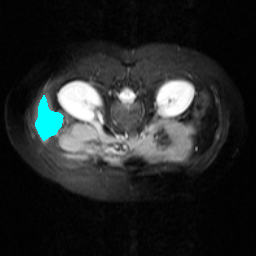

Support

Label

Proposed

In order to assess the performance of the proposed method, we compare the performance of the proposed model with excellent models in recent years. Table 1 and Table 2 shows the comparison results of different models in setting1, while Table 3 and Table 4 shows the comparison results of different models in setting2 on the data set in recent years. PANet[25] is the most widely influential few-shot model in the field of few-shot image segmentation on natural images. SENet [18] is the first few-shot segmentation model proposed for medical images. SSL-ALPNet[19] introduced the milestone of using superpixel self-supervision to train few-shot medical image models. RPNet[29] is a supervised method with a recursive mask optimization module to iteratively optimize the segmentation mask, [27] adapt it into the same self-supervision learning framework and applies setting1 to it and denoted as SSL-RPNet; CRAPNet[27] is the latest SOTA model for 2023. Compared with CRAPNet, our method outperforms most of the state-of-the-art models and only slightly outperforms CRAPNet. Figures 3 and 4 show examples of the model’s segmentation predictions on different datasets, respectively; The first row is the support map, the second row is the label map, and the third row is the segmentation prediction of the model.